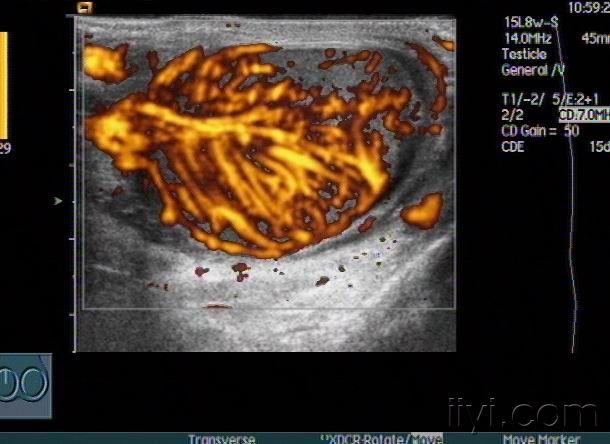

急性睾丸炎声像图——zengerya

急性睾丸炎声像图zengerya